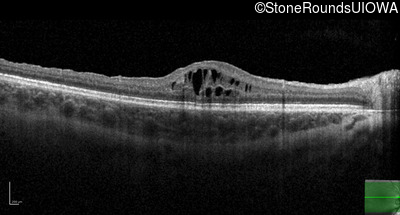

Optical Coherence Tomography - Right - 20/40 -2

Exemplar / OCT Stack